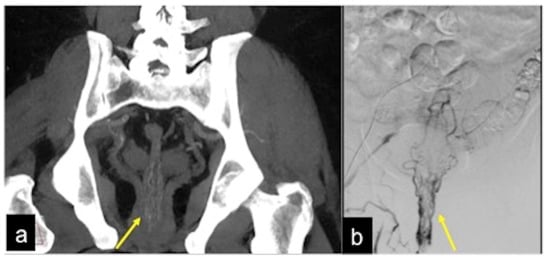

| Rectal Varices and Haemorrhoids (Figure 35) | Pain and/or bleeding. | Dilated veins with possible bleeding visible in the portal phase; rectal varices are located proximal to the linea dentata while haemorrhoids are located in the anus. |